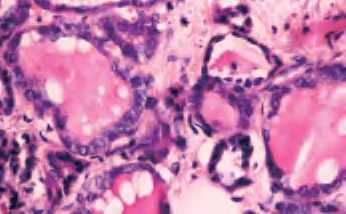

3.镜下 为复杂分支状乳头,含纤维血管轴心,细胞拥挤,核增大,呈卵圆形、沙砾体,表面被以单层柱状上皮,半数以上核呈毛玻璃样,有核沟,核内假包涵体(图3-40至图3-43)。

图3-40 甲状腺乳头状癌

图3-41 甲状腺乳头状癌

图3-42 甲状腺乳头状癌,箭头处核内假包涵体

图3-43 甲状腺乳头状癌,毛玻璃样核,箭头处为核沟